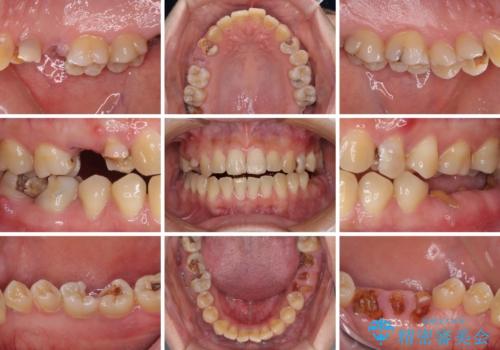

- 奥歯に問題が多くて困っているとのことで来院された患者様です。

開咬により奥歯のみが接触している状態で、前歯部にほとんど接触のない状態で、奥歯に非常に負担のかかる咬み合わせでした。

また、欠損や根管治療の必要な歯など、むし歯による問題も多く散見されました。

まずはむし歯の治療を行い、その後ワイヤー矯正にて咬み合わせを改善し、途中インプラント埋入を行い、矯正治療後に補綴治療を行うこととしました。

治療の期間と費用はかかりますが、初診時とは比べものにならないほど良好な状態にて治療を終えることができました。